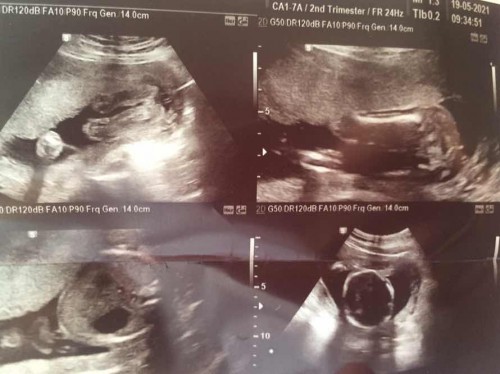

20w6d คุณหมอบอกน้องสมบูรณ์ดี นน.355g.

คุณหมอบอกว่าคุณแม่ได้ลูกสาว พอดีได้แผ่นปริ้นมาแบบนี้ แม่ดูไม่เป็นว่าส่วนไหน แม่ๆช่วยดูให้หน่อยค่ะ ว่าหมอได้ปริ้นส่วนที่เป็นเพศให้หรือเปล่า

รูปแรกค่ะ เหมือนเป็นหว่างขาน้อง

ผญ แน่เลย ดูจากรูปแรก